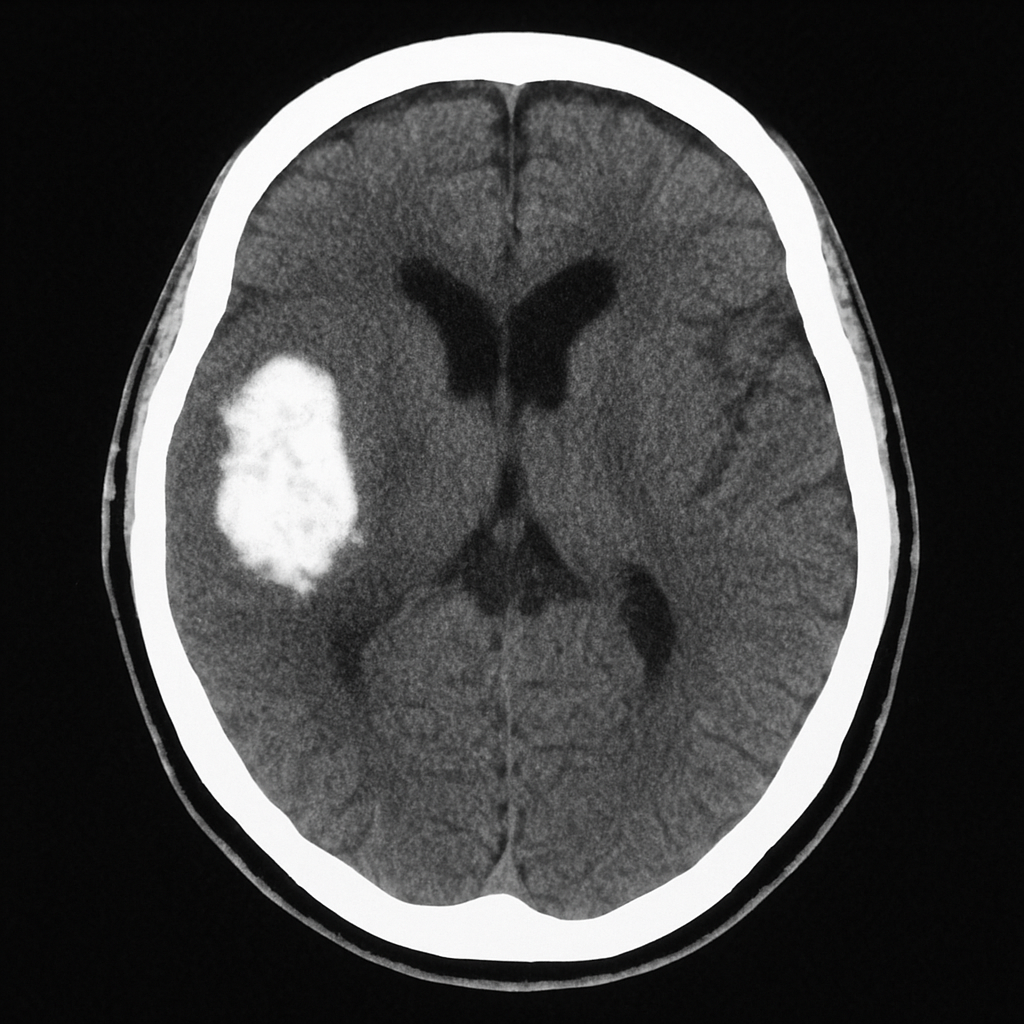

La hemorragia intracerebral, también llamada intraparenquimatosa, ocurre cuando se rompe un vaso sanguíneo dentro del tejido cerebral propiamente dicho. Es el tipo más frecuente entre las hemorragias cerebrales espontáneas.

Se diagnostica mediante tomografía computarizada (TAC) o resonancia magnética (RM).

El tratamiento puede ser médico (control de la presión intracraneal y la presión arterial) o quirúrgico en casos severos.